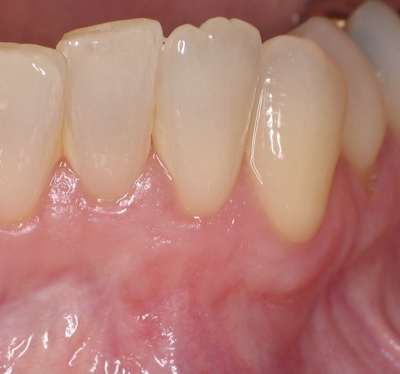

This is a before of a recession site.  A connective tissue graft was used.